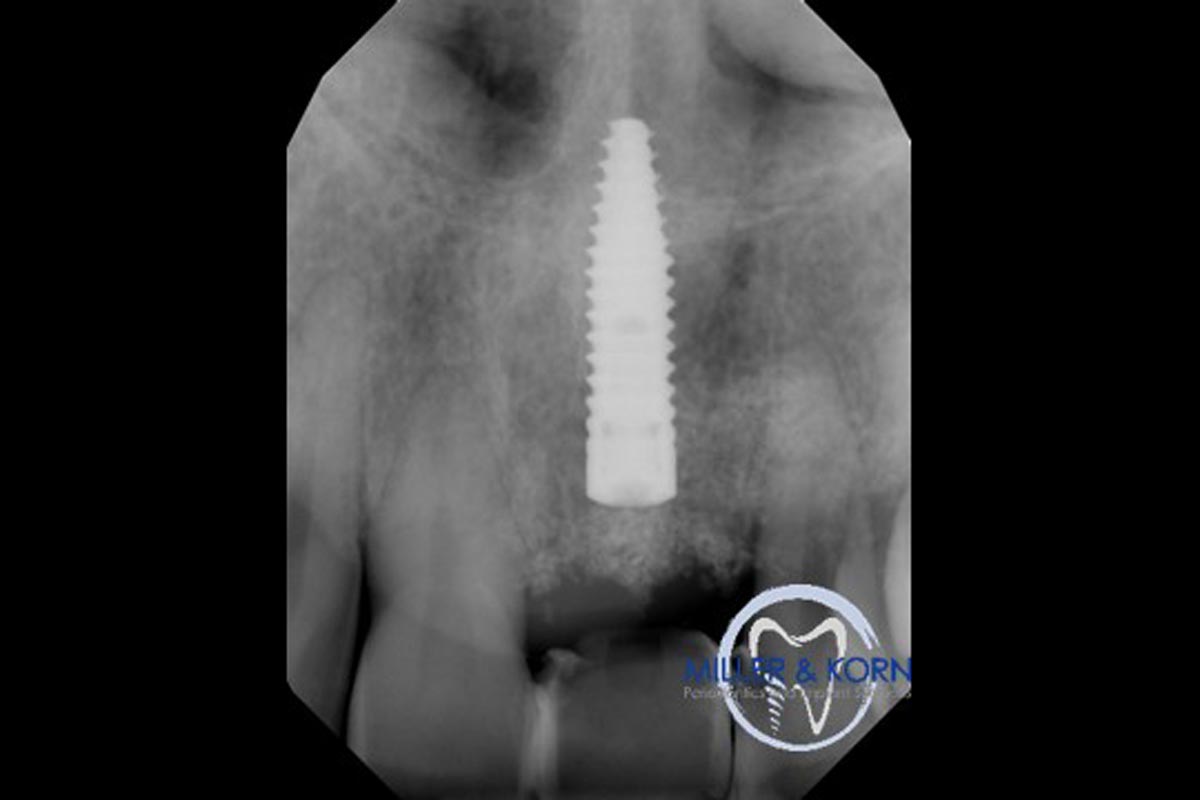

37/39 - Final radiograph revealing both horizontal and vertical augmentation of the osseous defects (8 months after implantation)Immediate implant placement and correction of horizontal and vertical bone loss using an allograft bone ring, cerabone® and Jason® membrane - Drs. Miller and Korn